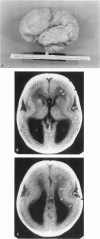

We report results of clinical, cytogenetic, and molecular studies in 27 patients with Miller-Dieker syndrome (MDS) from 25 families. All had severe type I lissencephaly with grossly normal cerebellum and a distinctive facial appearance consisting of prominent forehead, bitemporal hollowing, short nose with upturned nares, protuberant upper lip, thin vermilion border, and small jaw. Several other abnormalities, especially growth deficiency, were frequent but not constant. Chromosome analysis showed deletion of band 17p13 in 14 of 25 MDS probands. RFLP and somatic cell hybrid studies using probes from the 17p13.3 region including pYNZ22 (D17S5), pYNH37 (D17S28), and p144-D6 (D17S34) detected deletions in 19 of 25 probands tested including seven in whom chromosome analysis was normal. When the cytogenetic and molecular data are combined, deletions were detected in 21 of 25 probands. Parental origin of de novo deletions was determined in 11 patients. Paternal origin occurred in seven and maternal origin in four. Our demonstration of cytogenetic or molecular deletions in 21 of 25 MDS probands proves that deletion of a "critical region" comprising two or more genetic loci within band 17p13.3 is the cause of the MDS phenotype. We suspect that the remaining patients have smaller deletions involving the proposed critical region which are not detected with currently available probes.

Images in this article